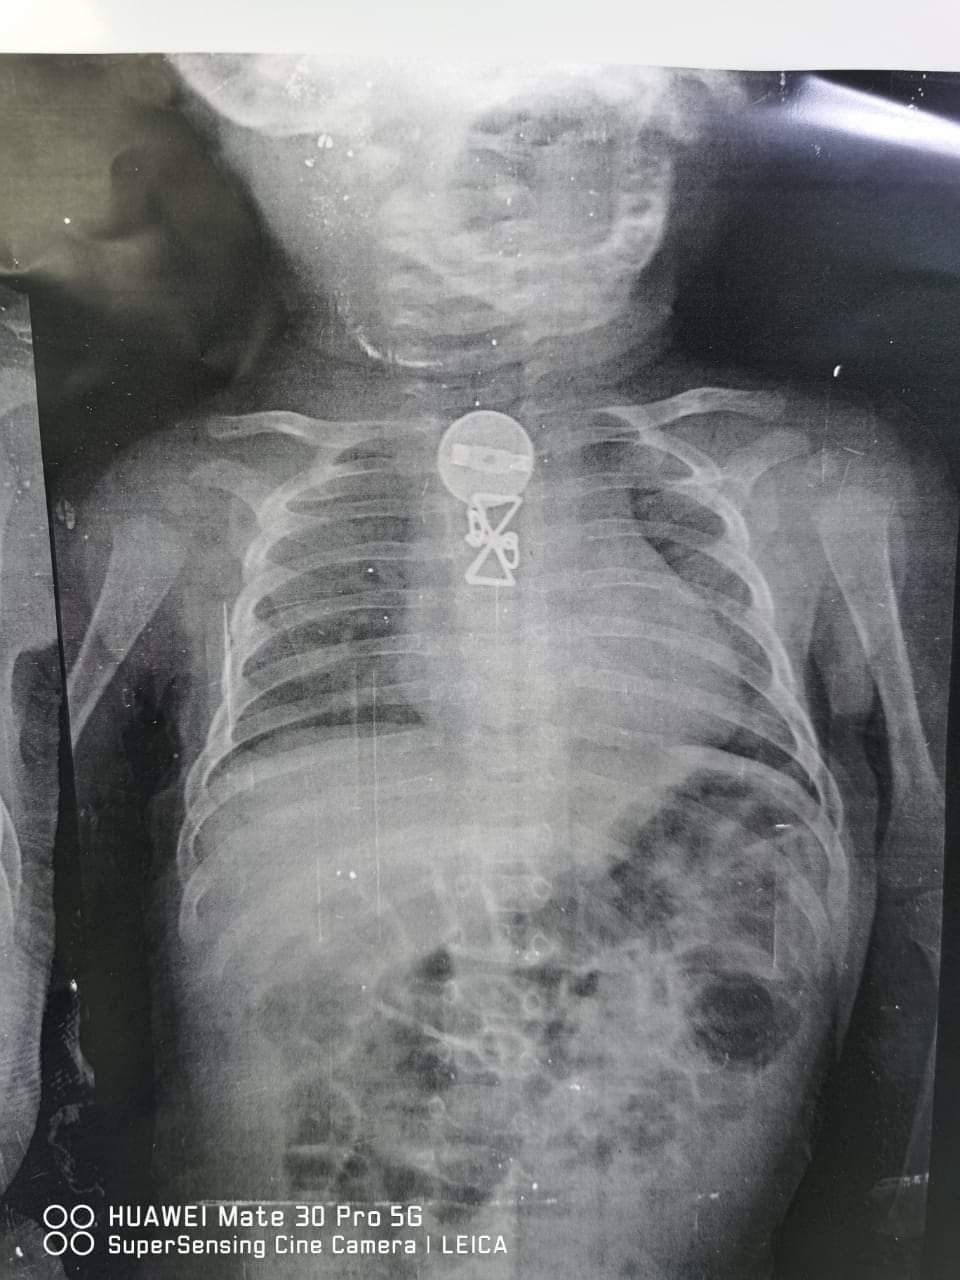

وأشار رئيس الفريق الطبي، أن المستشفى استقبلت الطفل وكان يعانى من التنفس وتم حجزه بالمستشفى وعمل الإشاعات اللازمة وتبين وجود جسم معدني داخل الجسد وتم استخراجه ، وتم العرض على والديه الذين أقروا ان شقيقته الكبرى كانت تداعبه و قام ببلع تلك الجسم المعدنى منذ فترة.